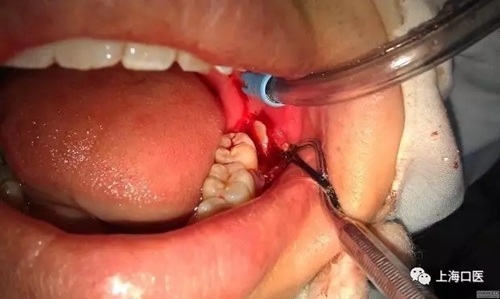

分牙

拔牙干槽癥可怕嗎?

我們拔牙時,能不用錘就不用,盡量減少創(chuàng)口,用錘分牙去阻的干槽癥發(fā)生率遠大于用手機分牙去阻的發(fā)生率,所用要多用手機,少用錘,用手機的時候也要注意,保護好牙周的軟組織,還有一點就是在分牙前一定要把手機中的潤滑油噴干凈,至少要讓手機先轉三分鐘,在很多拔牙術后,發(fā)生不明原因的疼痛,在一定程度上和手機殘留潤滑油有關,值得斟酌,且不管是否有關,只要我們做了工作,做好了細節(jié),自然可以減少患者疼痛的發(fā)生率的。細節(jié)決定成敗,一定要做好每一步工作,才能越趨于完美。